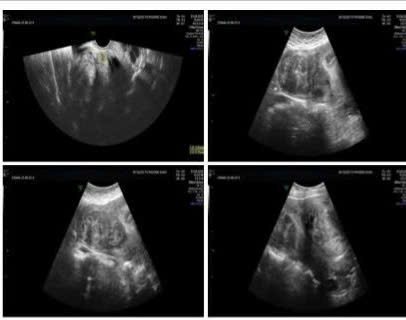

Qua thăm khám lâm sàng và siêu âm, bác sĩ phát hiện tử cung của chị to tương đương thai 12 tuần, với nhiều khối u xơ rải rác trong cơ và dưới thanh mạc ở thành sau tử cung, kích thước từ 3–5 cm. Xét nghiệm máu cho thấy chị bị thiếu máu mạn tính mức độ nhẹ (Hb 110 g/L, Hct 35.6%), nguyên u được cho là do tình trạng rong kinh kéo dài.

Hình ảnh: Siêu âm đa u xơ tử cung (L3, L4-5-FIGO). Nguồn: Bệnh viện Quốc tế Phương Châu

Sau khi hội chẩn, chị H được chẩn đoán mắc đa u xơ tử cung gây rong kinh và thiếu máu mạn tính. Chị bày tỏ mong muốn bảo tồn tử cung, và các bác sĩ đã thống nhất lựa chọn phương pháp phẫu thuật nội soi ổ bụng bóc u xơ tử cung. Đây là một ca phẫu thuật phức tạp do tử cung có nhiều khối u xơ kích thước lớn, tiềm ẩn nguy cơ mất máu cao, đòi hỏi phẫu thuật viên giàu kinh nghiệm.